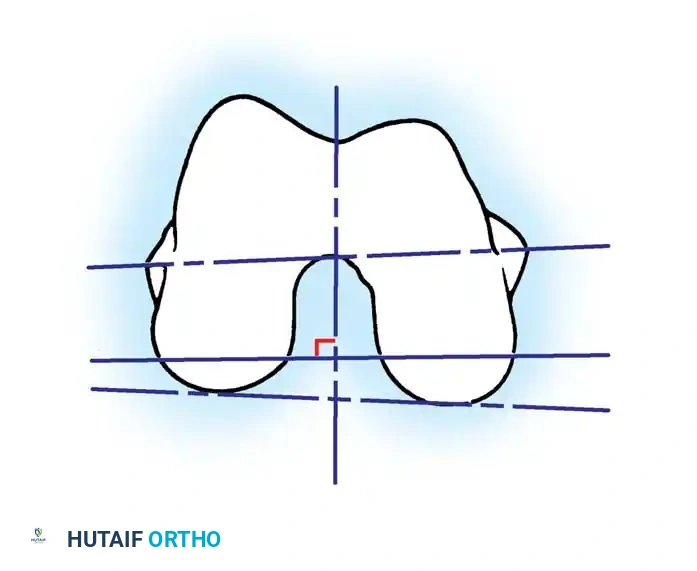

Femoral Rotational Alignment

The anterior and posterior femoral cuts determine the rotation of the femoral component and the shape of the flexion gap. This is arguably the most critical step in TKA.

Femoral component rotation can be determined using several anatomical and kinematic reference axes:

- The Surgical Transepicondylar Axis (TEA): Make the posterior femoral cut parallel to a line drawn between the prominence of the lateral epicondyle and the sulcus of the medial epicondyle.

- The Anteroposterior (AP) Axis (Whiteside's Line): Draw a line from the deepest part of the trochlear groove to the center of the intercondylar notch. The posterior femoral cut is made perpendicular to this axis.

- The Posterior Condylar Axis (PCA): When referencing the posterior condyles, the cut is typically made in 3 degrees of external rotation relative to a line connecting the most posterior aspects of the medial and lateral condyles.